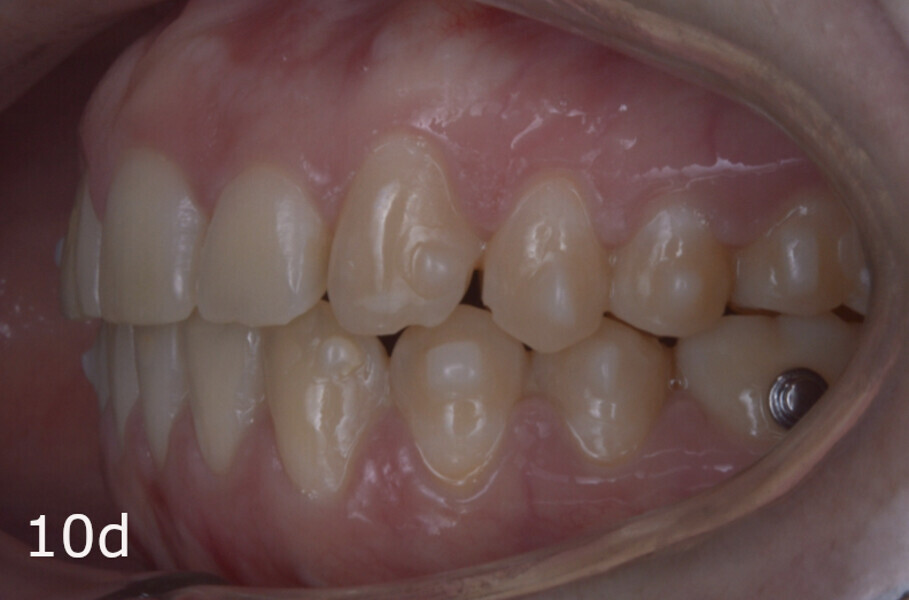

The treatment objectives included closing the anterior open bite, achieving a bilateral Angle Class I relationship and a proper overjet and overbite, correcting the midline discrepancies, and achieving a profile harmonisation. The treatment plan consisted of orthodontic camouflage treatment with asymmetric distalisation in three of the four quadrants using Invisalign aligners (Align Technology) and third molar extraction. The Invisalign Comprehensive package was chosen, and 63 pairs of aligners were used (Figs. 7–10). Each aligner was worn for 20 hours a day for one week each. The use of Class III elastics on both sides was indicated. Afterwards, ten refinement aligners were needed to improve the interdigitation on the right side (Figs. 11 & 12).

The total treatment time was 15 months. An Angle Class I relationship was established along with adequate anterior and canine guidance, establishing a functional occlusion. This not only ensures optimal masticatory function but also protects the teeth and the temporomandibular joint from excessive force. Maxillary and mandibular fixed retention were installed at the end of the treatment (Figs. 13–19).